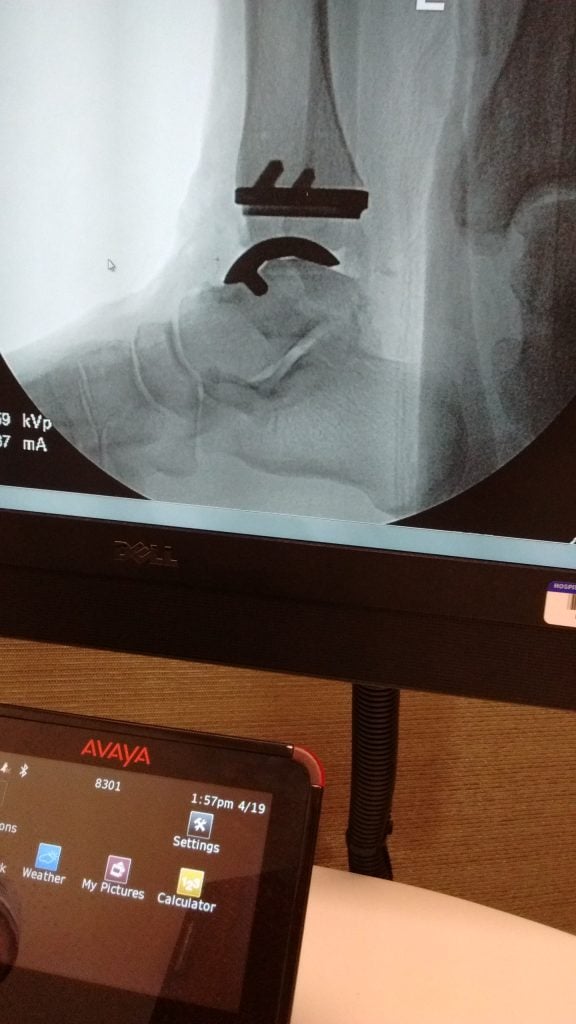

In 2016, a local foot and ankle surgeon referred me to Dr. Ellis for ankle replacement surgery on both ankles. I tried alternatives to surgery for a while, but in the end scheduled an appointment with Dr. Ellis when walking any distance became too painful. I had my left ankle replacement in 2018 and the second replacement on my right ankle 18 months later. Dr. Ellis gave me my life back. Before surgery, every step was painful and I was extremely limited in what I could do. After a several month recovery for each surgery, I can golf, hike, climb stairs and walk for miles pain-free. I am very thankful to the initial specialist I saw, who both recognized what I needed and that it required the specialized care provided by Dr. Ellis at HSS. That is why I give annually in gratitude for my “new” ankles.